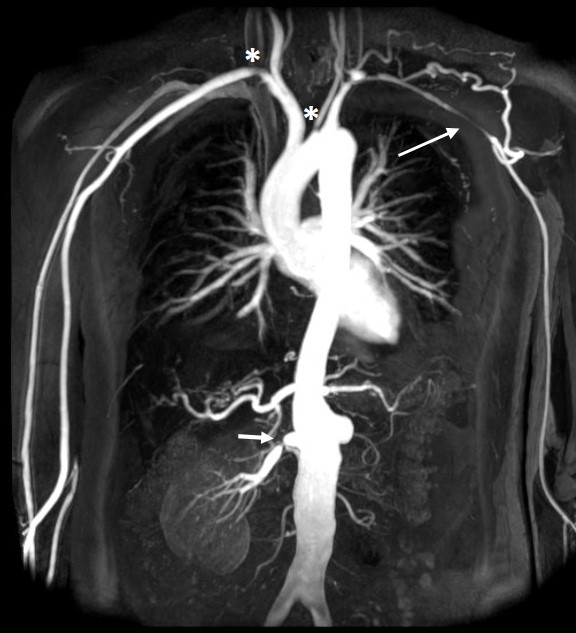

The boy was suffering from Juvenile Takayasu Arteritis, an extremely rare inflammatory disorder that attacks the body’s largest artery — the aorta — and its branches. The disease had caused severe narrowing of blood vessels, leaving his heart functioning at only 15% capacity and nearly cutting off blood supply to both kidneys.

Open-heart surgery was considered too dangerous. So the doctors opted for a high-risk minimally invasive procedure, using ultra-thin catheters and real-time vascular imaging.

The team inserted precision-guided stents to widen the blocked aorta and renal arteries — restoring blood circulation without opening the chest.

Takayasu Arteritis is often called “the pulseless disease” because it can silently block major arteries — leading to stroke, heart failure, or death. It is extremely rare in children, making timely diagnosis and treatment difficult.